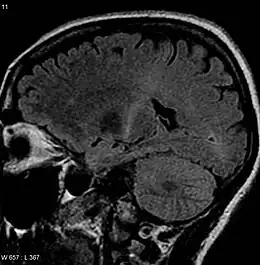

Sclérose latérale amyotrophique

(coupe sagittale en pondération T2 FLAIR).